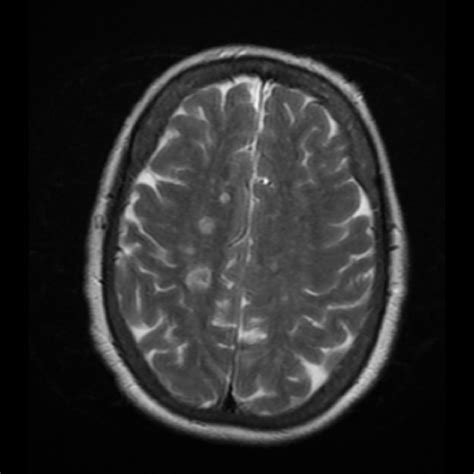

• Imaging Tests: Imaging tests such as MRI or CT scans may be used to visualize the brain and spinal cord for any abnormalities.

• Neuroimaging Studies: Advanced neuroimaging techniques can provide insights into the brain and spinal cord abnormalities that contribute to the condition.